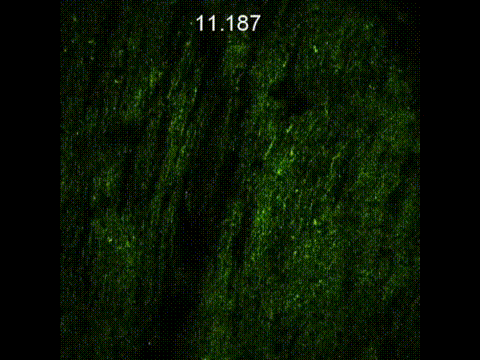

JadeBio is a fluorescent confocal imaging system that combines real-time, high-speed, and high-resolution scanning. It meets the imaging needs of independent laboratories or biomedical institutions. It can perform three-dimensional imaging of optical slices by upgrading and integrating with the existing fluorescent microscope system. Combining the modules with high sensitivity and high dynamic contrast, it can achieve high-resolution, low-destructive, and low-photobleaching sample observations in contrast to using a few watts of fluorescent excitation light source, and thus achieving more accurate, long-term, and complete 3D biological sample signal. By the integration of the XYZ platform for large image stitching, you can see the full picture of a large area of biological microscopic images. With the support of Southport’s rich spectroscopy experience, the biological optical measurement methods have been expanded. JadeBio can be upgraded to Raman spectroscopy, time-resolved spectroscopy, and other applications needed by the next generation. In addition, with the support of super-resolution optical technology, Southport SRM is currently possible to surpass the traditional optical limit. In the near future, we expect to reach a resolution of 100 nm or even 50 nm and overcome the limitation of requiring special dyes or special excitation methods.

By the advantages of multi-photon imaging technology, JadeBio can inspect various living samples and directly observe physiological phenomena such as the repairing phenomenon of mouse hair follicles, the distribution of mouse brain nerves, and the pathological condition of the eye surface cells of the mouse, etc...

The living organism is the most direct observation of biological samples, and it is also the most direct proof of biological tissue disease or repair status change. A good imaging system requires a platform with a large degree of freedom so that the optical system can directly perform high-resolution and long-term imaging on the organs or tissues of the organism. JadeBio provides such an interface so that all biological live images can be easily captured.